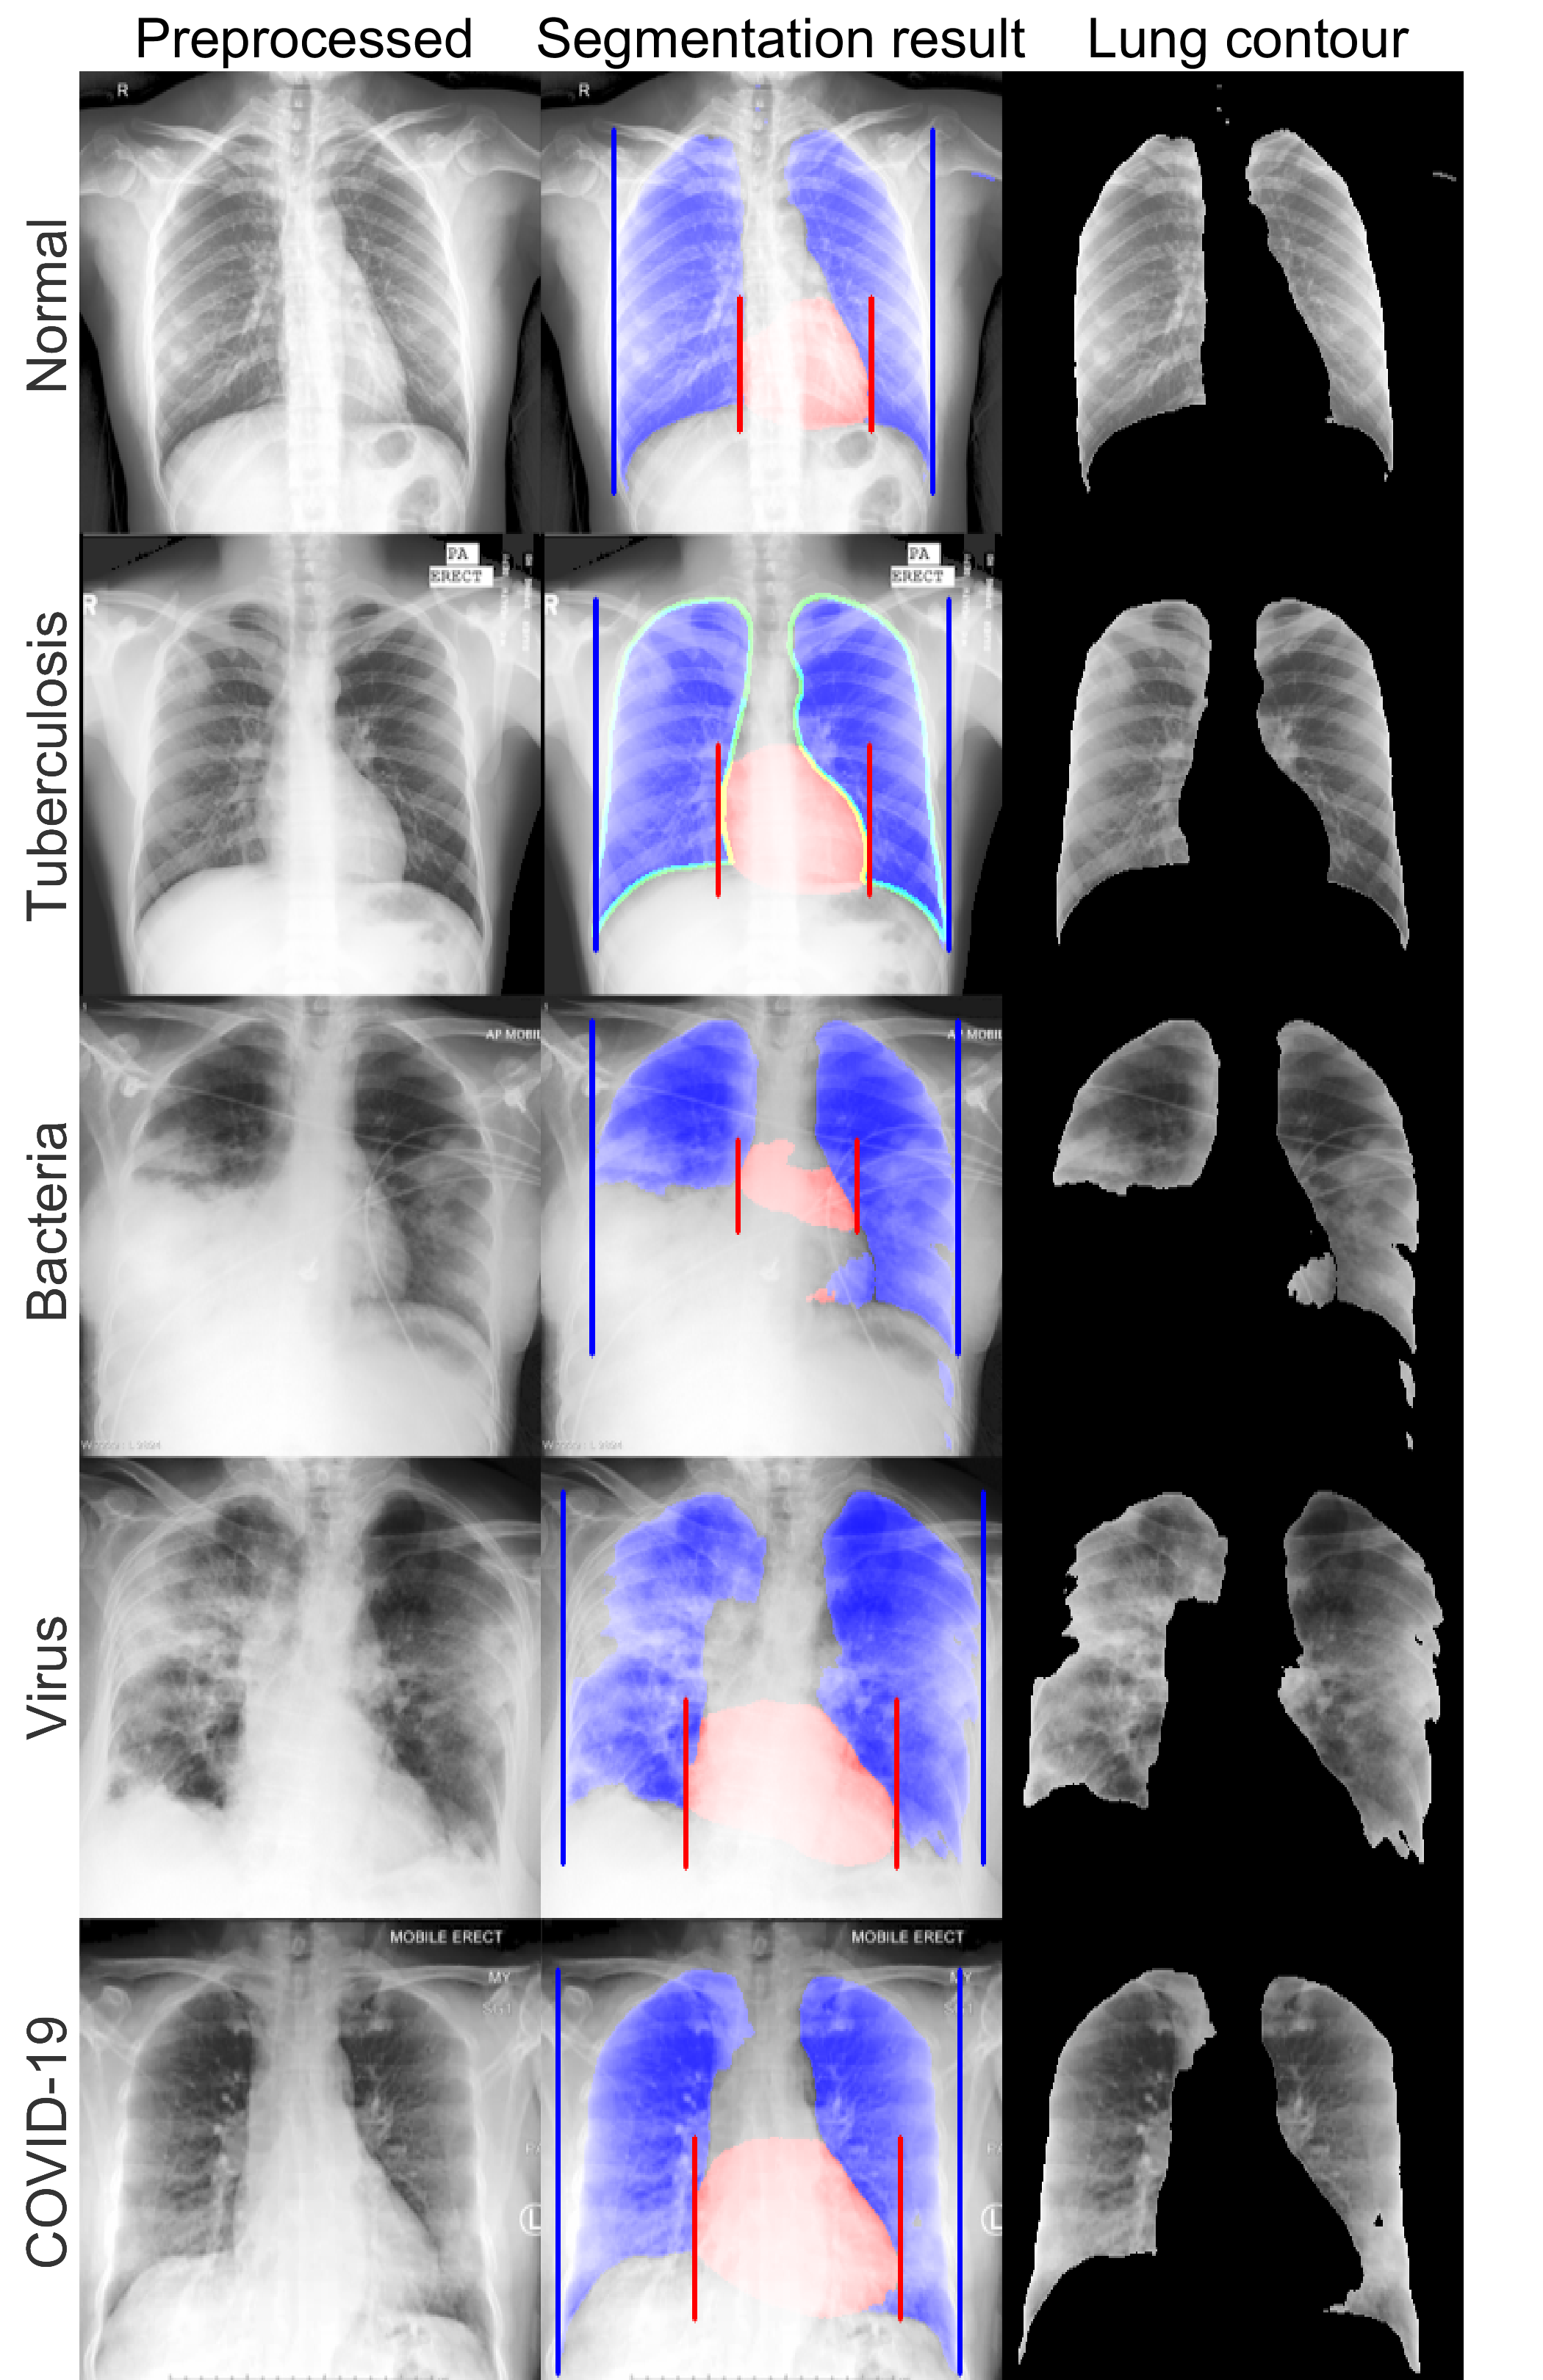

IV-B Morphological analysis of lung area

To analyze morphological characteristics in the segmented lung area, a representative CXR radiograph for each class was selected for visual evaluation. Lung contour of each class showed differentiable features and showed mild tendency. In normal and tuberculosis cases (the first and the second row of Fig. 3, respectively), overall lung and heart contour were well-segmented. In the bacterial case, however, the segmented lung area was deformed due to wide spread opacity of bacterial pneumonia as shown in the third row of Fig. 3, and both the right cardiac and thoracic borders were lost. In overall bacterial infection cases, similar findings were occasionally observed which caused degraded segmentation performance. This suggests that abnormal morphology of the segmentation masks may be a useful biomarker to differentiate the severe infections. In the fourth row of Fig. 3, viral infection caused bilateral consolidations [29], thus partial deformation of lung area was observed. In the COVID-19 case of the fifth row of Fig. 3, despite the bi-basal infiltrations [30], lung area was fully segmented. In overall cases of the viral and the COVID-19 classes, lung areas were either normally or partially-imcompletely segmented, so morphological features of the segmentation masks may not be sufficiently discriminatory markers for viral and COVID-19 classes. Based on these morphological findings in segmented lung area, we further investigated other potential COVID-19 biomarkers.